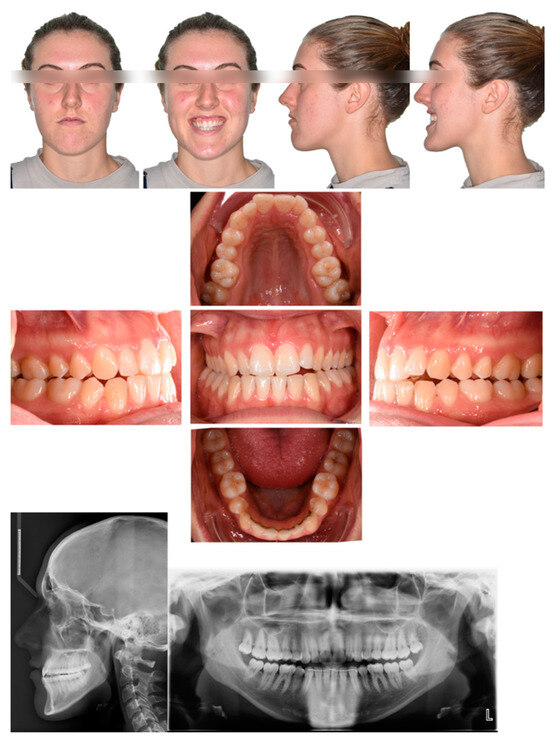

2.1. Diagnosis and Individual Treatment Planning

2.2. Clinical Preparations